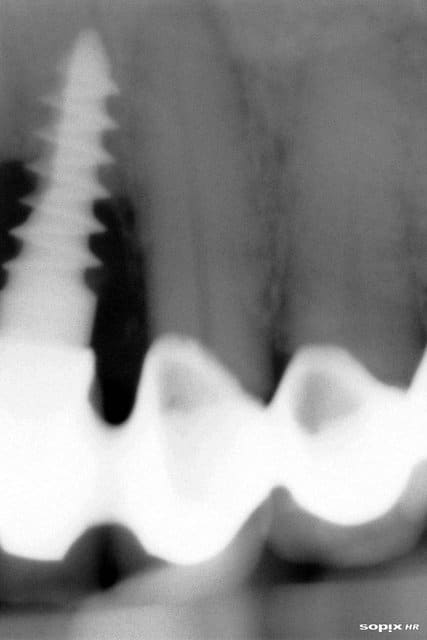

Je vous joins une panoramique, j'ai dû faire une capture d'écran, j'espère que c'est lisible.

Patient la cinquantaine, pas d'ATCD médicaux, fumeur occasionnel, motivé, du tartre en pagaïe.

Reconstruction par deux bridges complets, dento-implanto-portés, effectuée de l'autre côté de la frontière par praticiens français.

Le travail a environ 18 mois sur cette radio.

pour ceux que çà intéresse...c'est des implants trinon...;-)

Mêmes vis à bois. Mêmes péri-implantites.

Je connais pas grand chose en implantologie.. mais il me semble que , ici, il y a TOUT ce qu'il ne faut SURTOUT pas faire, non ?

Implant mal enfoui, limite cervicale anti-anatomique

Hybride dent naturels/implant, à éviter à tout prix.

Implant trop prêt de la racine d'une dent naturelle.

Notions d'hygiène absentes.

autres..

perte du capital osseux et financier